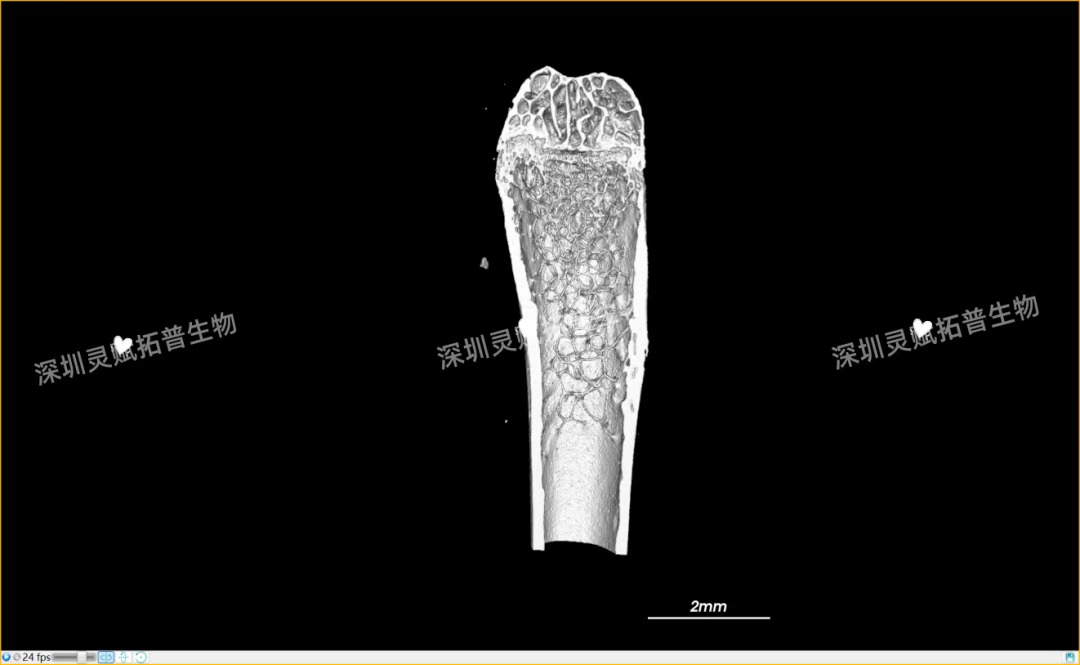

以小鼠股骨检测为代表,带大家直观感受EVO视讯集团生物的服务实力:

本次实验对 E2 系列(E2-1、E2-2、E2-3)共3个小鼠股骨样本进行标准化扫描,取得了 0.5mm、2mm 等不同尺度的清晰成像,不仅直观呈现了股骨的宏观形态,更精准捕捉到骨小梁排列、皮质骨厚度等微观细节,为后续骨质疏松、骨修复等相关研究给予了可靠的量化数据支撑。

下附E2系列的典型案例:小鼠股骨扫描成像图